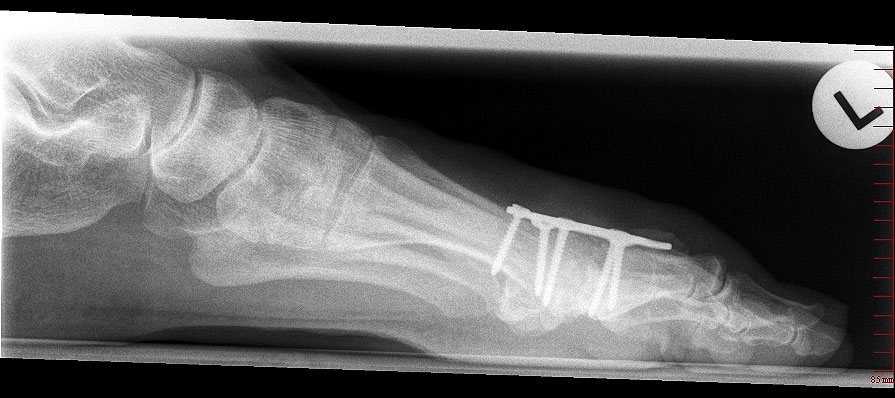

Das nachfolgend präsentierte OP-Verfahren zeigt die Großzehengrundgelenkarthrodese mit Gelenkflächenpräparation mittels sogennanter „Cup-and-Cone“-Fräsen und einer dorsal angebrachten variablen winkelstabilen Platte mit Gleit-/Kompressionsloch.

Durch die Verwendung sogenannter „Cup-and-Cone“-Fräsen und die Osteosynthese mit winkelstabiler Platte ggf. in Kombination mit einer interfragmentären Zugschraube kann die Rate der Pseudarthrosen vor allem bei schlechten Knochenverhältnissen deutlich reduziert werden, sodass dieses Verfahren zunehmend empfohlen wird 9.

• Röntgen-Kontrolle der Osteosynthese und Stellung intraoperativ / postoperativ, nach 3 Wochen und nach 6 Wochen